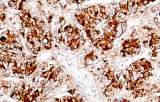

CE/IVD antibodies for immunohistochemistry (IHC) in neuropathology are validated in vitro diagnostic reagents used to detect specific neuronal and glial antigens in formalin-fixed paraffin-embedded (FFPE) tissue. Peer-reviewed neuropathology literature supports their role in improving reproducibility and diagnostic accuracy in central nervous system (CNS) diseases, including brain tumors and neurodegenerative disorders.

Targeted proteins such as GFAP, OLIG2, NeuN, synaptophysin, neurofilament, and Iba1 reflect astrocytic, oligodendroglial, neuronal, and microglial lineages. Their expression patterns are widely used in peer-reviewed studies to define CNS cell identity, differentiation state, and neuroinflammatory or degenerative processes.

CE/IVD IHC antibodies support CNS tumor classification (gliomas, embryonal tumors, metastases), assist in differential diagnosis, and help identify proteinopathies associated with Alzheimer’s disease and other neurodegenerative conditions. They are routinely used in biomarker panels for tumor grading and diagnostic stratification in neuro-oncology.